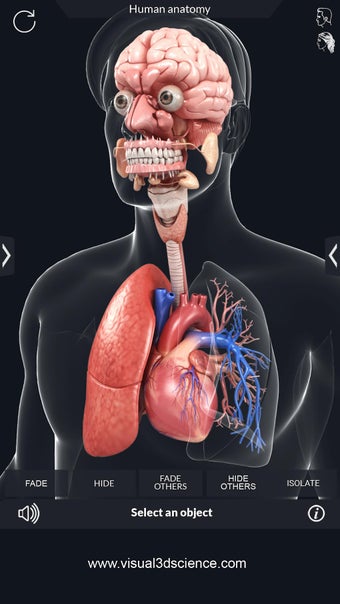

Una aplicación gratuita para Android, creada por Visual 3D Science.

La anatomía humana es una aplicación educativa médica que te permite explorar el cuerpo humano desde todos los ángulos. Ofrece una mirada detallada a la anatomía de los diferentes sistemas, así como a los órganos y sus funciones. Es una referencia perfecta para estudiantes y profesores de medicina.

Puedes seleccionar cada parte del cuerpo por separado para ver su nombre o leer información relacionada. Puedes ocultar y mostrar cada parte del cuerpo, así como rotar 360° alrededor de un modelo 3D altamente realista. Puedes dibujar en la pantalla o compartir capturas de pantalla con tus amigos. Puedes encontrar la definición de cada parte del cuerpo y su anatomía.